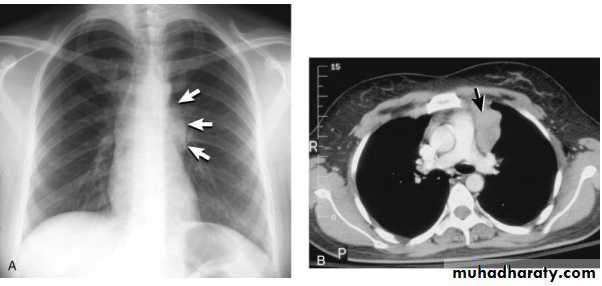

Thymoma.

A chest x-ray (A) reveals an unusual contour over the left hilum (arrows). That the hilum is not obscured (no silhouette sign) indicates that the mass must either be in front of or behind the hilum. A computed tomography scan (B) reveals a soft tissue mass (arrow) just to the left of the aorta. This is the most common location of a thymoma.